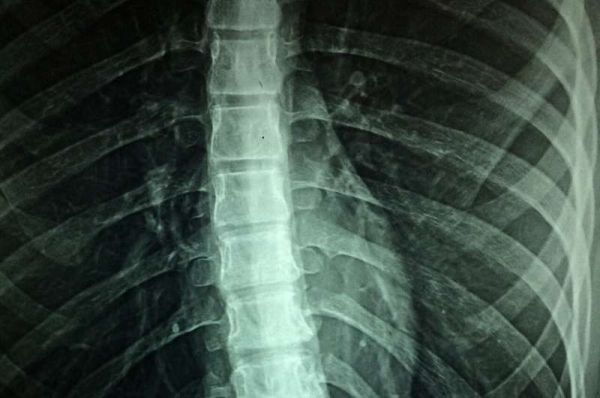

Ba năm trước, TS. Gill bị chấn thương cổ trong một vụ tai nạn ván lướt nằm (boogie board) khi đi nghỉ cùng gia đình. Hầu hết mọi người đều biết rằng, để đi lại, bệnh nhân sẽ cần phải sử dụng phương tiện xe lăn hỗ trợ. Tuy nhiên, đối với những người bị chấn thương tủy sống (SCI), những gì diễn ra bên trong cơ thể gây ảnh hưởng nghiêm trọng đến chất lượng cuộc sống của họ.

Trong nghiên cứu này, nhóm nghiên cứu sử dụng kích thích điện ngoài màng cứng có mục tiêu (EES) của tủy sống để ổn định huyết động (lưu lượng máu đi khắp cơ thể) cho phép các cơ quan quan trọng duy trì nguồn cung cấp máu thích hợp. Họ phát hiện ra vị trí chính xác trên cột sống cho hệ thống kích thích và mạch của hệ thần kinh giao cảm cơ bản kiểm soát huyết áp. Kiến thức mới này cho phép các nhà nghiên cứu phát triển một hệ thống thông tin liên lạc vòng kín thần kinh giả, để thay thế sự kiểm soát huyết động đã mất.